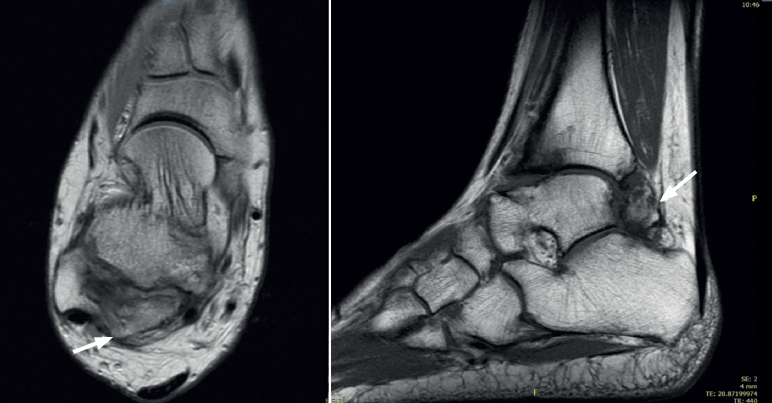

Es una entidad rara de etiología desconocida que afectaría a 1 de cada millón de personas, es 3 veces más frecuente en el varón y presenta el aspecto clínico e histológico de un osteocondroma que asienta en la epífisis en vez de la zona metafisaria del hueso en crecimiento(24,25)(Figuras 4 y 5).

En adultos (Figuras 6 y 7), se cita como causa de pinzamiento doloroso en la cámara posterior del tobillo(50), aunque también como causa de impingement anterior(51), o confundirse con un osteocondroma a pesar de sus diferencias histológicas. Mientras el osteocondroma reproduce una arquitectura similar a la de la placa de crecimiento, la displasia epifisaria hemimélica muestra en su cubierta cartilaginosa áreas con acúmulos de condrocitos y pequeñas áreas de cartílago calcificado no reabsorbido(52). Por otra parte, la presencia de osteocondromas en la parte posterior del astrágalo es muy rara. En una serie de 7 casos en los que se produjo rotura a través del pedículo en relación con ejercicio físico, Carpintero et al. no señalan ninguna en esta localización(53).

Aunque suele diagnosticarse antes de los 8 años de edad, puede tener un carácter asintomático y no ser detectada en la infancia, si bien suele producir dolor, alteraciones de los ejes o dismetría de los miembros. Aunque no se han descrito casos de degeneración maligna, en su evolución tardía puede sufrir fracturas, trastornos mecánicos en la articulación afectada y en el caso del astrágalo una artropatía degenerativa de tarso y tobillo(27).

Se caracteriza por un sobrecrecimiento epifisario en alguna zona de este hueso que forma una tumoración que crece hasta que se alcanza la madurez esquelética, sobre los 12 años.